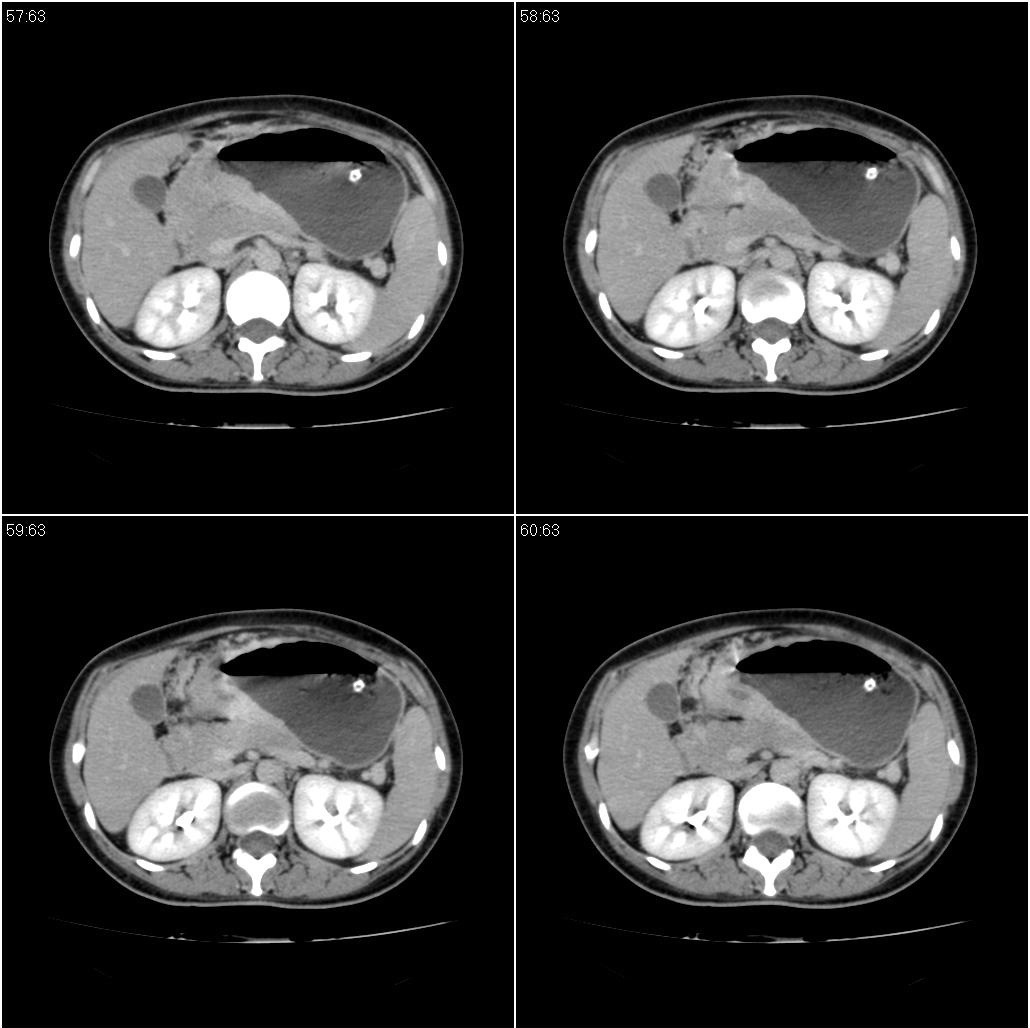

标题: CT21386:女性,33岁。4个月前因妊娠发现盆腔肿物。 [打印本页]

女性,33岁。4个月前因妊娠发现盆腔肿物。ca-125: 1100

胃幽门部癌伴小弯侧和腹腔淋巴结转移,胃内有胃管。

胃窦贲门胃小弯好像都厚啊 ,胃窦处比较明显,而且胃腔扩张明显,考虑胃癌伴梗阻。

胃壁局限性增厚,支持肿瘤性病变伴周围脓肿形成可能

未见明显肿大淋巴结,另肝脾大

支持;胃癌【浸润】幽门梗阻.胰头、胆囊及肝左叶受侵,副脾.

考虑胃窦占位并肝门部淋巴结转移

考虑胃窦部胃癌伴小弯侧和腹腔淋巴结转移。

胃幽门部癌伴小弯侧和腹腔淋巴结转移,胃内有胃管